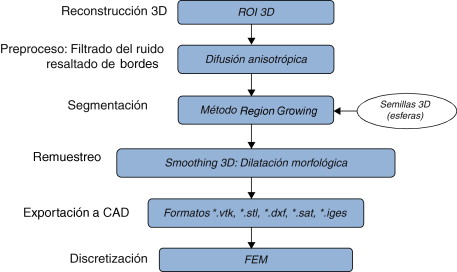

3.3. Modelado de la materia blanca

El cerebro, como todas las partes del sistema nervioso central contiene una sustancia blanca y una sustancia gris, siendo la última la de menor cantidad. La segmentación de estas estructuras permite realizar un análisis cuantitativo morfométrico necesario para el diagnóstico de distintas patologías y en la evaluación de la respuesta a un determinado tratamiento. Sin embargo, esta tarea se ve afectada por la presencia de distintos tejidos con niveles de gris similares, la ausencia de valores constantes en los niveles de gris. Asimismo, las imágenes médicas del cerebro como las IRM y las PET, entre otras, presentan ruido característico asociado a este tipo de imagenología.

La técnica de segmentación Region Growing puede resultar útil para extraer este tipo de sustancias cerebrales debido a la flexibilidad del método para indicar pequeñas zonas iniciales en los tejidos que se desean segmentar a través de la selección de semillas, asimismo, es posible controlar y restringir las zonas que se van sumando en cada interacción del algoritmo, estableciendo características más sofisticadas como la combinación de la media, la desviación estándar, la entropía, la correlación, entre otros clasificadores estadísticos.

En este caso de estudio seleccionado, el volumen de la zona de la materia blanca fue obtenido aplicando el flujograma de algoritmos presentado en la figura 19 .

|

3.3.1. Preproceso

El ruido de las imágenes fue filtrado empleando el algoritmo de difusión anisotrópica, suavizando así el ruido y preservando los bordes de la imagen. De esta manera se consiguió mantener los contornos que dividen la materia blanca de los demás tejidos y uniformizar sus valores de gris.

3.3.2. Segmentación

Se aplicó el algoritmo Region Growing sobre la imagen filtrada, colocando cuatro esferas (semillas) en la zona de interés, buscando ubicarlas en los extremos más arraigados de este tejido. La condición de inclusión utilizada para hacer crecer la región fue la descrita en la ecuación (10), en base a la media y la desviación estándar de los voxels vecinos. El volumen resultante fue una imagen binaria con la zona de la materia blanca coloreada en valores de 255 (blanco).

3.3.3. Remuestreo y exportación a CAD

Para mejorar el modelo geométrico inicial, se realizó el remuestreo del volumen a través de dilatación morfológica con un elemento estructural en forma de esfera de radio 3 × 3 × 3 a lo largo de todo el tejido segmentado. Este paso es necesario para suavizar superficies superpuestas y rellenar los agujeros generados durante la segmentación debido a la sensibilidad de la condición de segmentación. El modelo geométrico final fue guardado en formatos legibles por software de visualización y herramientas CAD como GiD, ParaView, Autodesk Inventor y Abaqus.

En la figura 20 se presentan los resultados obtenidos por cada etapa en imágenes médicas de IRM del cerebro en formato DICOM, 60 slices , tamaño de 256 × 256 pixels, voxel spacing: 0,86 × 0,86 mm × 3,0 mm . Por efectos de visualización, solamente se presenta uno de los cortes axiales utilizados. Obsérvese en la figura 20 .b la selección de cuatro semillas sobre la zona de interés, las cuales fueron asignadas de manera arbitraria. El éxito de la segmentación dependerá del lugar donde se coloquen estas semillas.

Figura 20. Segmentación de materia blanca empleando Region Growing en IRM del cerebro. (a) Volumen de IRM cerebral original. (b) Vista de un corte axial con la lección de cuatro semillas iniciales. (c) Imagen (b) filtrada con difusión anisotrópica. (d) Vista del corte axial (b) con la materia blanca segmentada a través de Region Growing . (e). Vista volumétrica de la materia blanca segmentada en (d). |